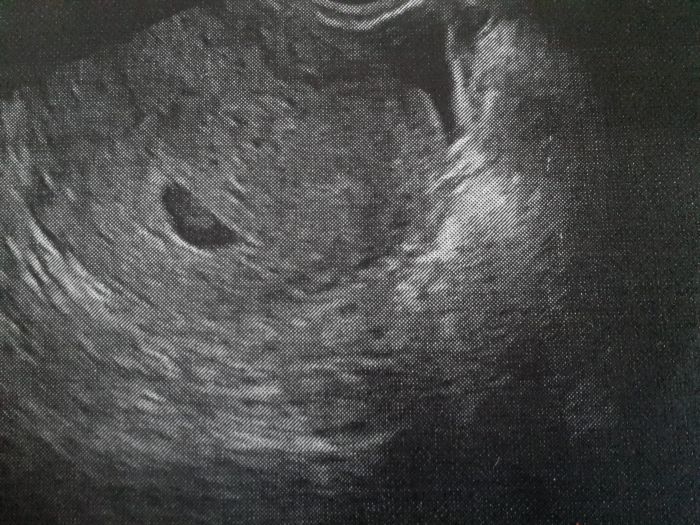

Jinak ja dneska taky byla na kontrole a uz sem videla mimi na utz, sice jenom takovej flicek, ale je to mimi a dr videla i srdicko, jak tluce, tak snad je zatim vsechno v poradku :-) dalsi injekci sem neska nedostala, ale kdybych zacla spinit, tak mam prej hned prijit, tak snad to bude dobry...zkusim prilozit fotku z utz, ale je tam videt fakt jenom flicek :-)

[1016015] Luci, podle ms su 6+1 a podle utz 5+6 :-) tak snad to bude vsechno dobry :-)